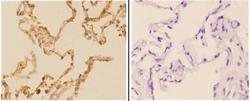

- Immunohistochemistry validation of ACHE using Anti-Acetylcholinesterase AChE Antibody (A03519). Immunohistochemistry (IHC) analyzes of AChE pAb bin paraffin-embedded human lung carcinoma tissue at 1:50

- Additional image